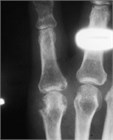

Acute gout is a painful arthritis caused crystalline deposition; it commonly affects patients in their 40s-60s. Although any joint can be affected it is classically described in the MTP of the great toe (Podagra). The differential includes septic arthritis and in a first-time flare or if red flag symptoms are present (such as fever) an arthrocentesis may be required. There are several analgesic options that include NSAIDs, corticosteroids (either PO or IM), colchicine or even narcotic pain medication in severe cases. For recurrent attacks lifestyle modification/medication to reduce uric acid should be considered.